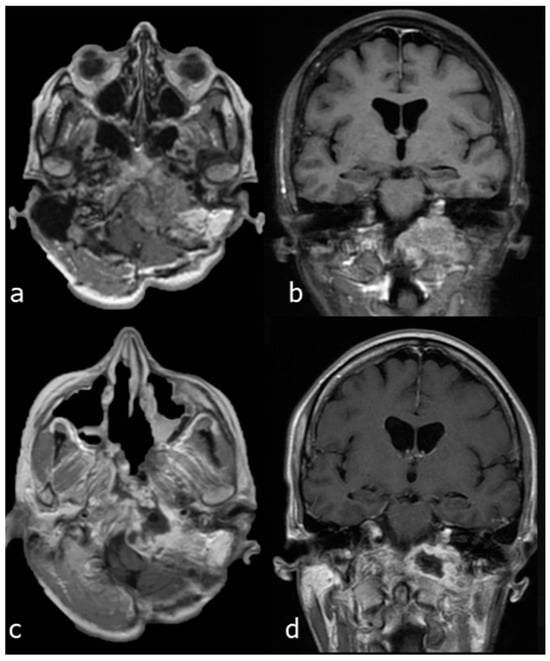

- Case 3